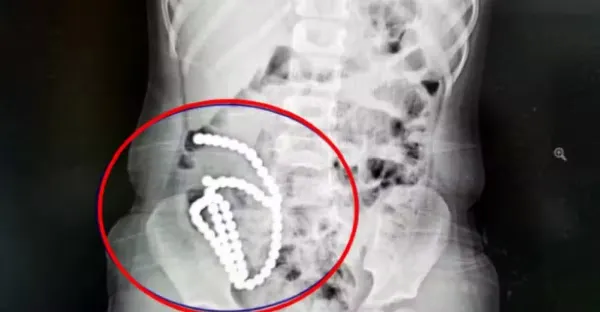

4歲妹妹照X光驚見「肚子整串白珠珠」 媽證實哥哥在玩!醫嘆:一輩子毀了